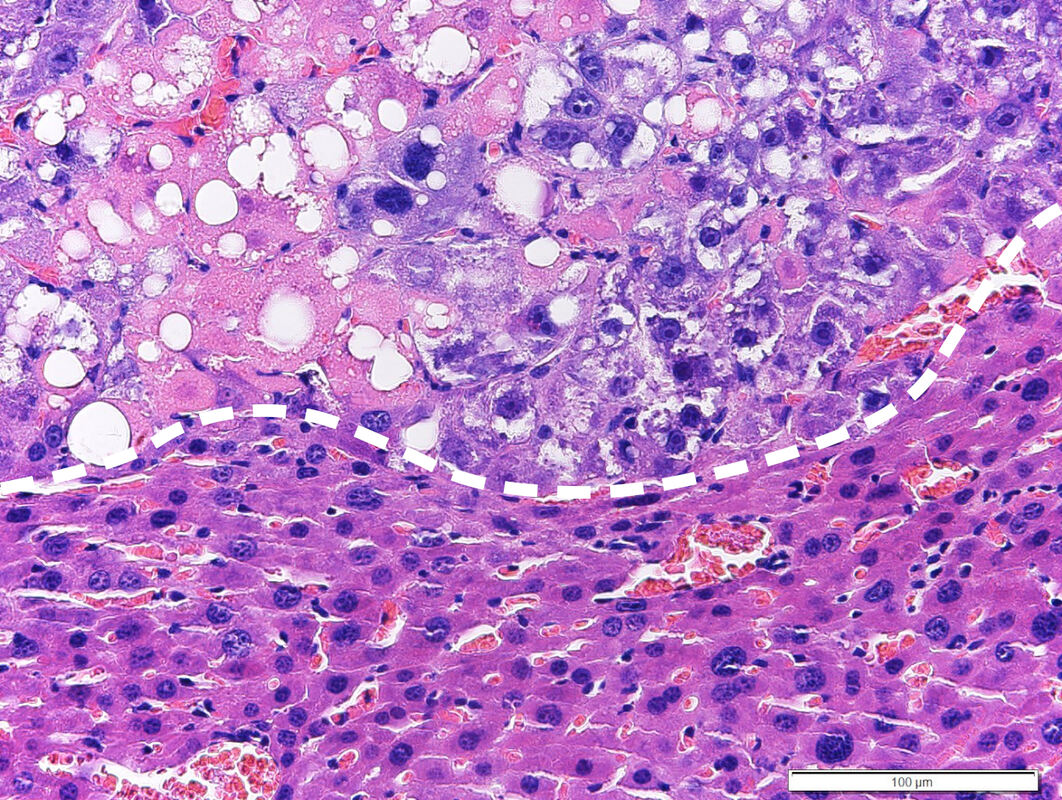

Beim neuen Ansatz wird therapeutisch in den Fettstoffwechsel der Tumorzellen eingegriffen. Durch Aktivierung des sogenannten LXR-Proteins kommt es zur Steigerung der Fettsäuresynthese. Diese kann zunächst von der Tumorzelle toleriert werden, weil anfallende gesättigte Fettsäuren (aus der Ernährungsmedizin auch als schlechte Fettsäuren bekannt) kontinuierlich durch ein Enzym zu ungesättigten (guten) Fettsäuren umgewandelt werden. Wird jedoch gleichzeitig ein zweites Protein, die sogenannte Raf-1 Kinase, gehemmt, so kommt es in der Tumorzelle zu einer Anreicherung von gesättigten Fettsäuren, welche von der Tumorzelle nicht toleriert werden kann und zum Zelltod der Tumorzelle führt. Von besonderer Bedeutung ist, dass das neue Therapiekonzept eine starke Wirksamkeit gegen Leberkrebs hat, welcher durch Leberverfettung (NASH) hervorgerufen wird. Klinische Studien haben gezeigt, dass diese sogenannten NASH-HCCs mit den derzeitigen zielgerichteten oder Immuntherapien nur schwer zu beherrschen sind.